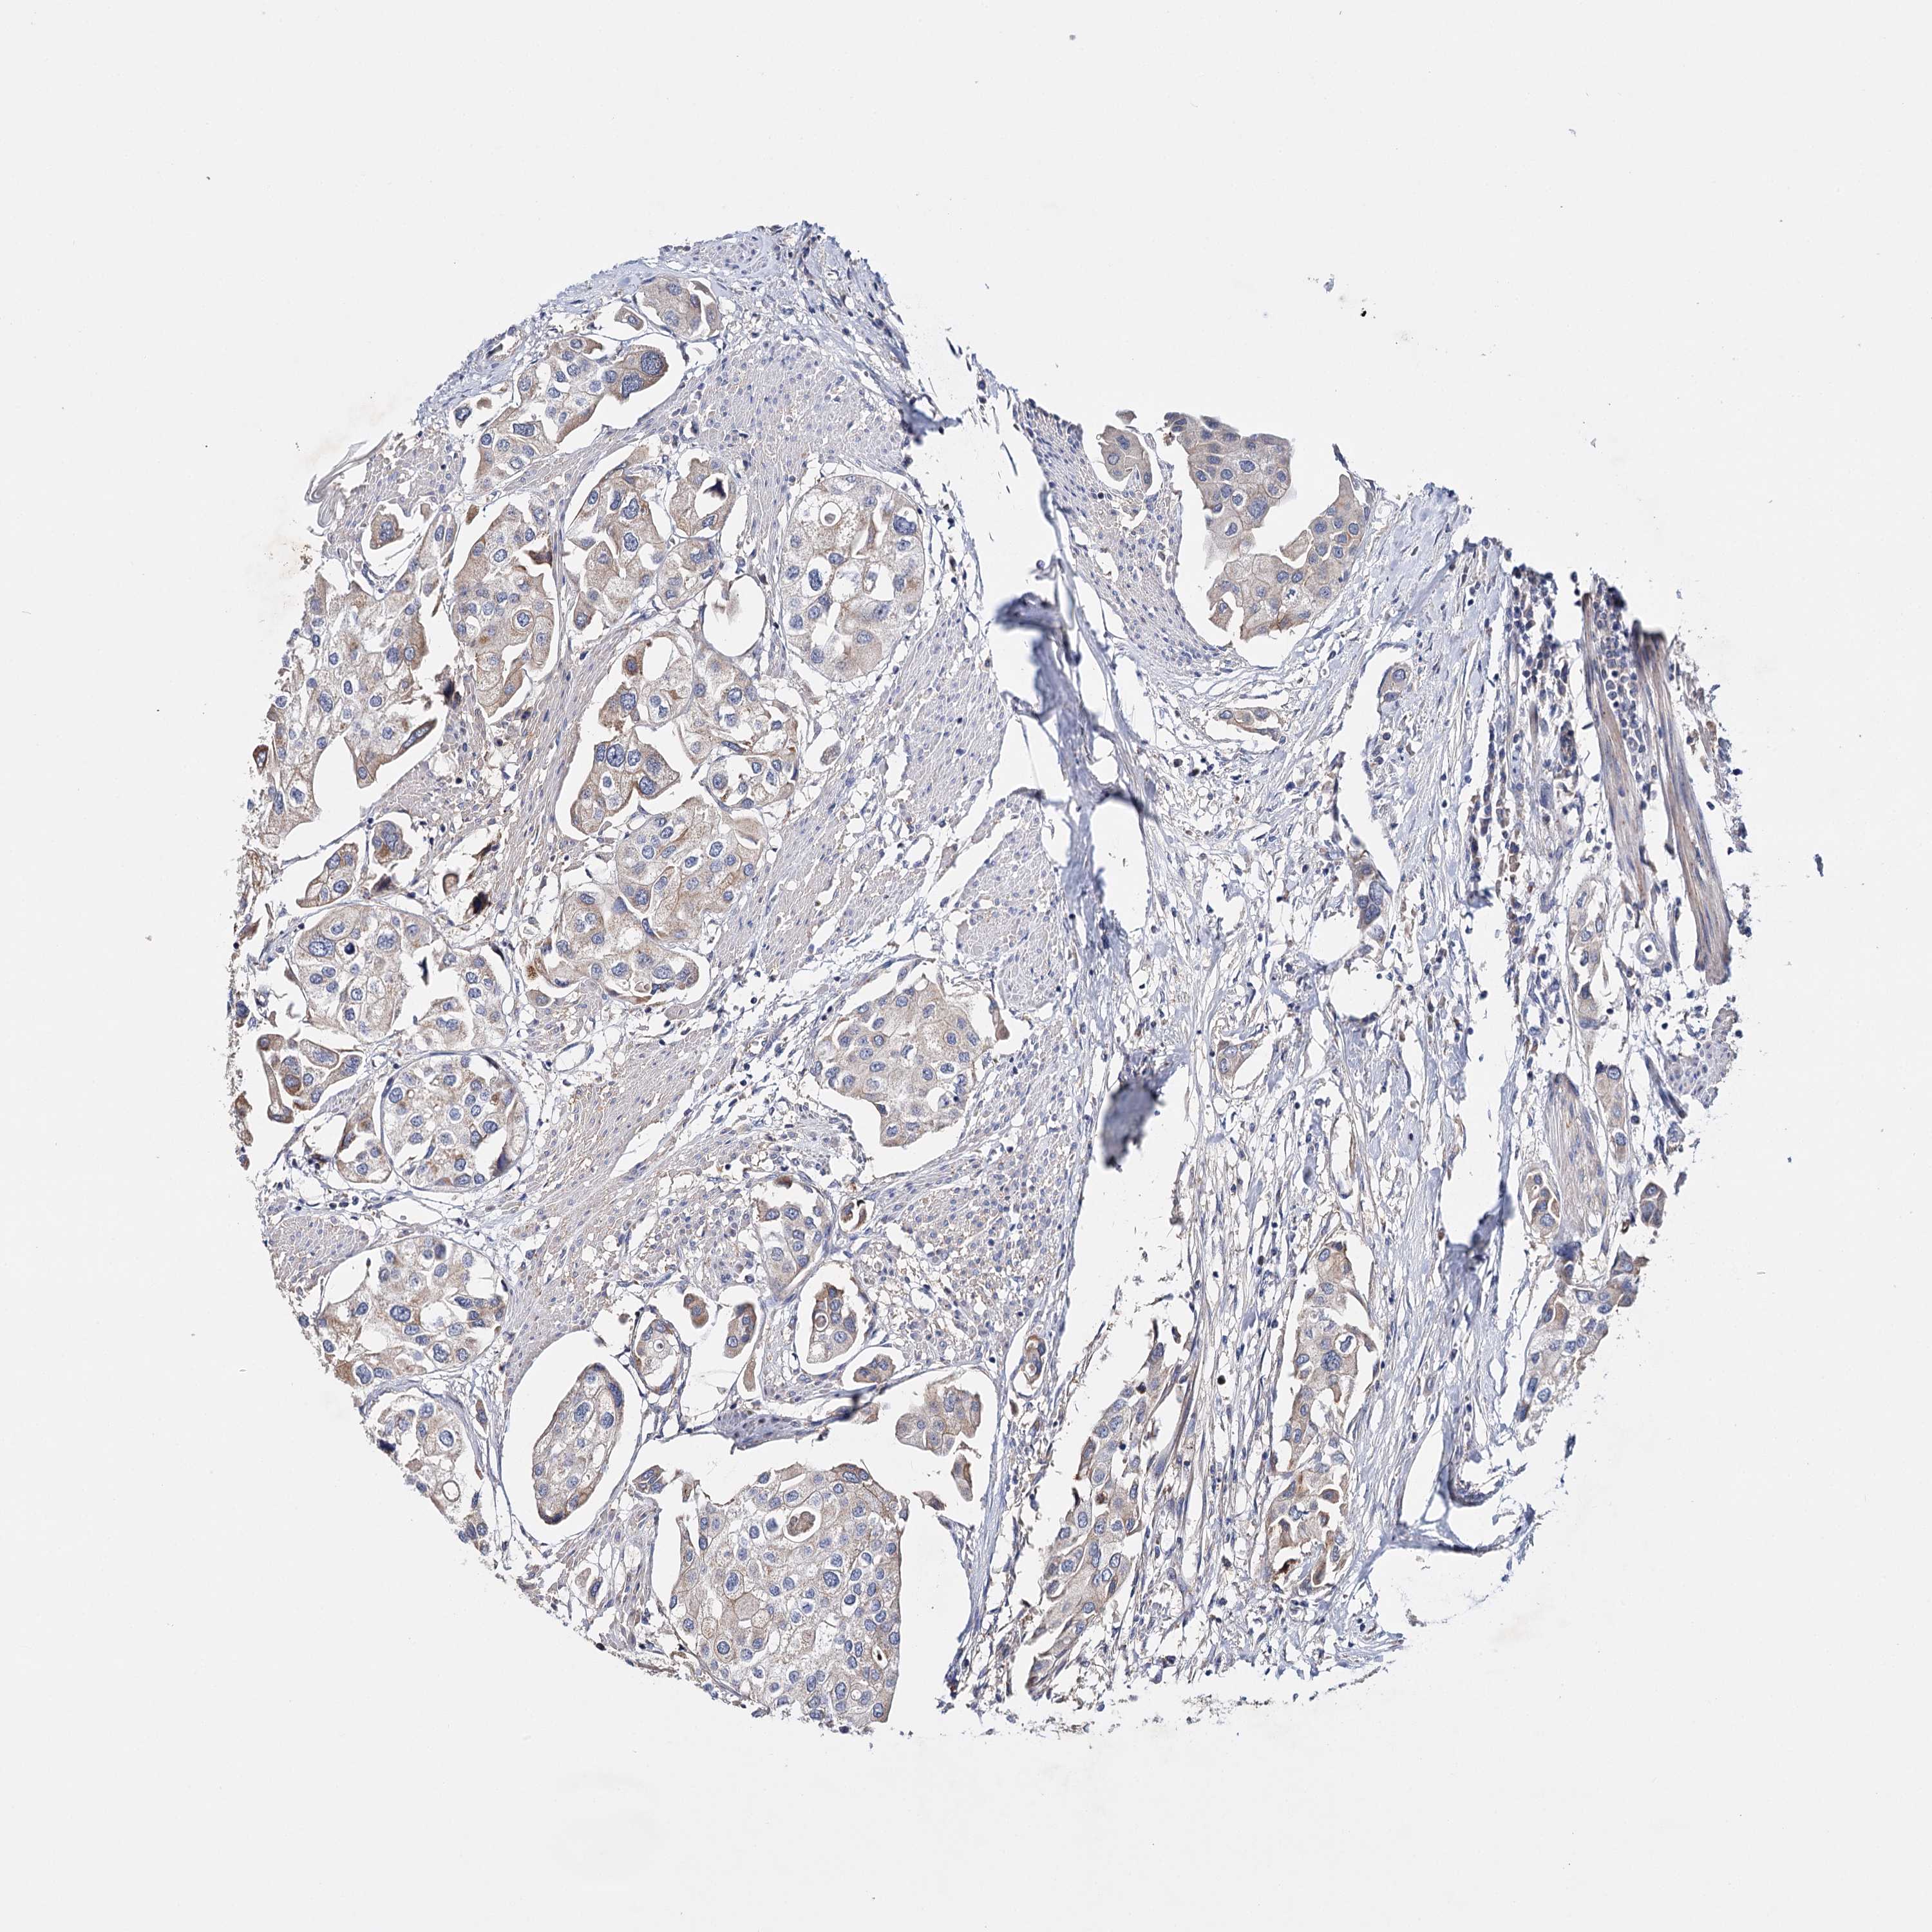

UROTHELIAL CANCER - Protein expressioni

A mouse-over function shows sample information and annotation data. Click on an image to view it in a full screen mode. Samples can be filtered based on level of antibody staining by selecting one or several of the following categories: high, medium, low and not detected. The assay and annotation is described here.

Note that samples used for immunohistochemistry by the Human Protein Atlas do not correspond to samples in the TCGA dataset.

Antibody stainingi

Antibody staining in the annotated cell types in the current human tissue is reported as not detected, low, medium, or high, based on conventional immunohistochemistry profiling in selected tissues. This score is based on the combination of the staining intensity and fraction of stained cells.

Each image is clickable and will lead to virtual microscopy that enables deeper exploration of all samples and also displays staining intensity scores, fraction scores and subcellular localization as well as patient and tissue information for each sample.

Antibody HPA037786

Antibody HPA038034

Antibody HPA038867

Antibody HPA038868

Staining

High

Medium

Low

Not detected

Intensity

Strong

Moderate

Weak

Negative

Quantity

>75%

75%-25%

<25%

None

Location

Nuclear

Cytoplasmic/membranous

Cytoplasmic/membranous,nuclear

Urothelial carcinoma, High grade

Urothelial carcinoma, Low grade

Urothelial carcinoma, NOS